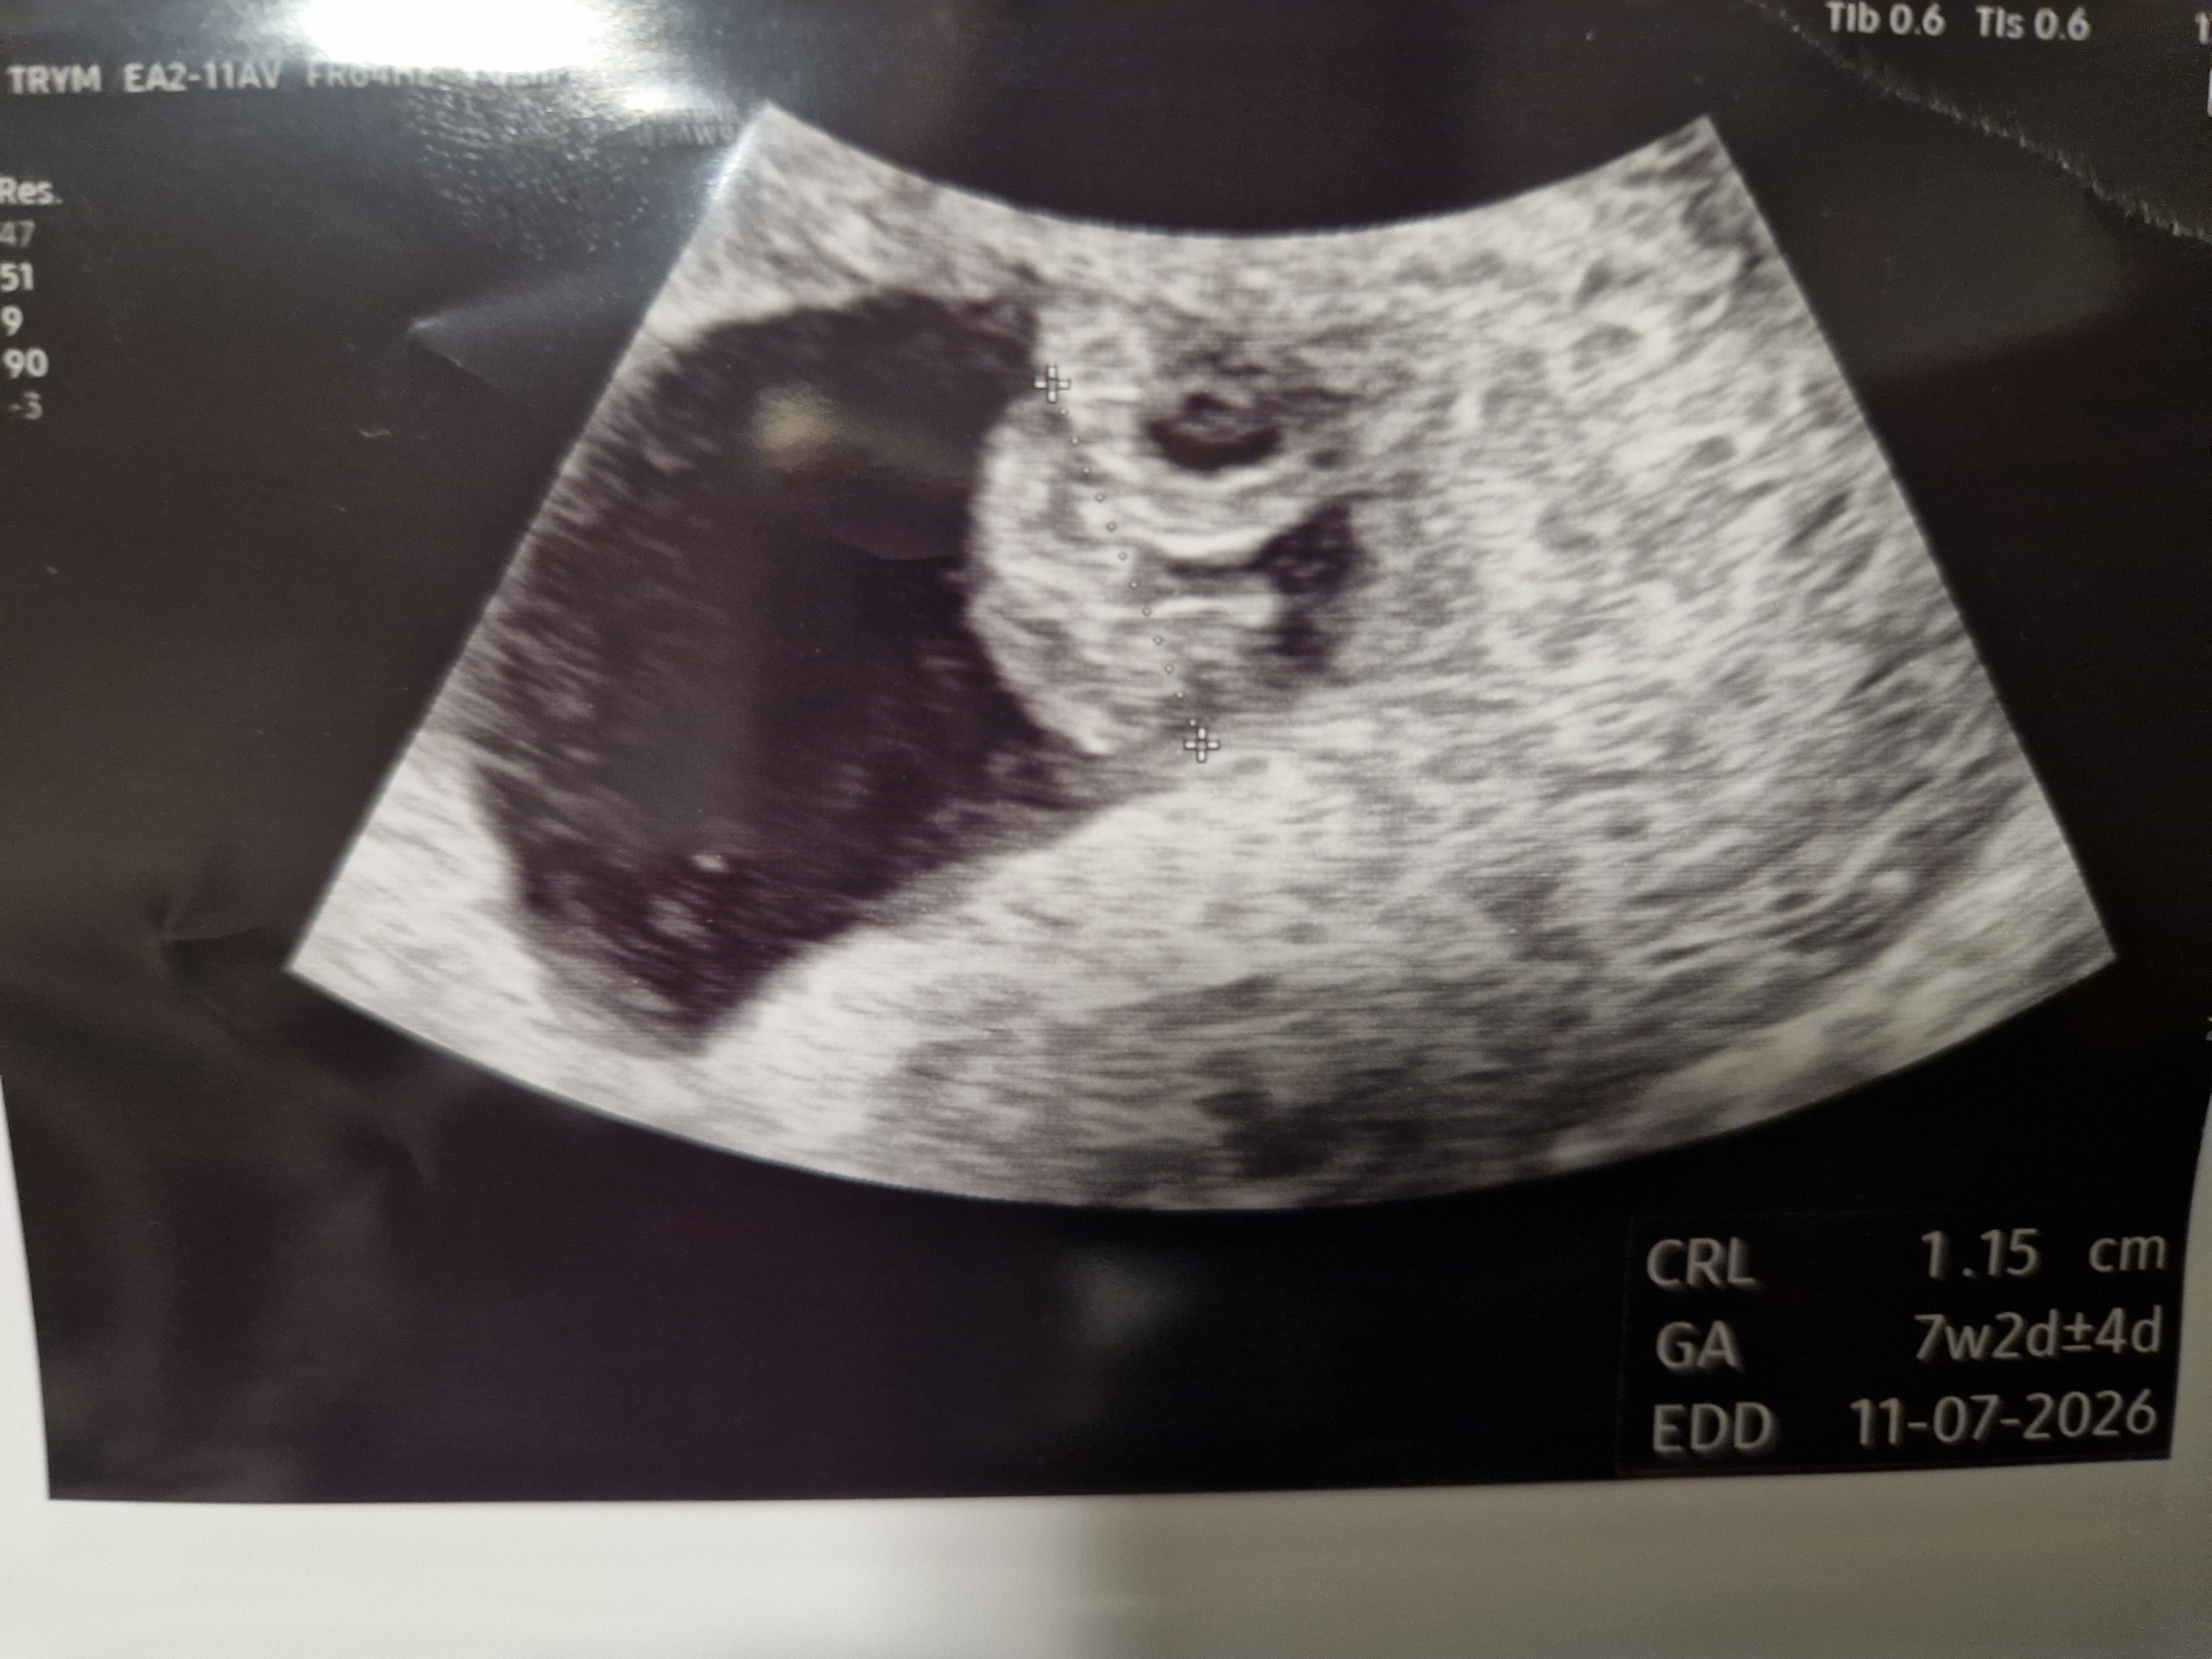

Jestem już po wizycie, jest ❤️

Z USG 15 lipca termin. Za dwa tygodnie kolejna wizyta żeby zobaczyć czy wszystko nadal będzie ok i dopiero wtedy będziemy zakładać kartę ciąży

Jestem już po wizycie. Jest serduszko, bije 143 bpm ❤️ krewecia wygląda jakby miała ręce na zdjęciu 😁